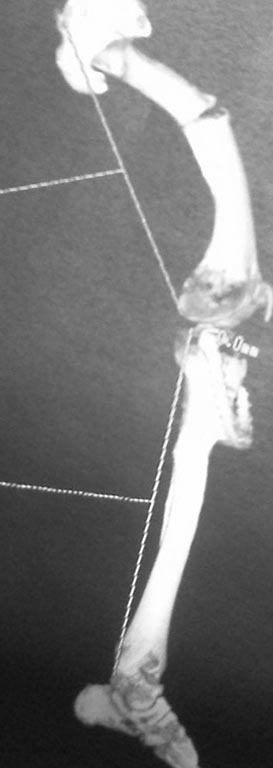

Re: перелом бедра с исходной деформацией

Посмотрите, подойдёт ли туда по размеру гвоздь от большой берцовой кости или от плеча. Они покороче и могут подойти, так как канал у пациента короткий и широкий. Гвоздь будет тонким, по сравнению с его каналом, но этого будет достаточно для стабилизации. Если есть машина Midas Rex с насадками для резки железа, то можно и обычный гвоздьь для бедреной кости подрезать и просверлить в нём дырку дистально.

А про nail даже и не думайте - канал кривой-косой, очень широкий и короткий

Максим, рассмотрите вариант с TEN максимального диаметра. Наблюдали двоих пациентов, возраст 20 и 18 лет, результат положительный. Штифт будет как "в стакане"